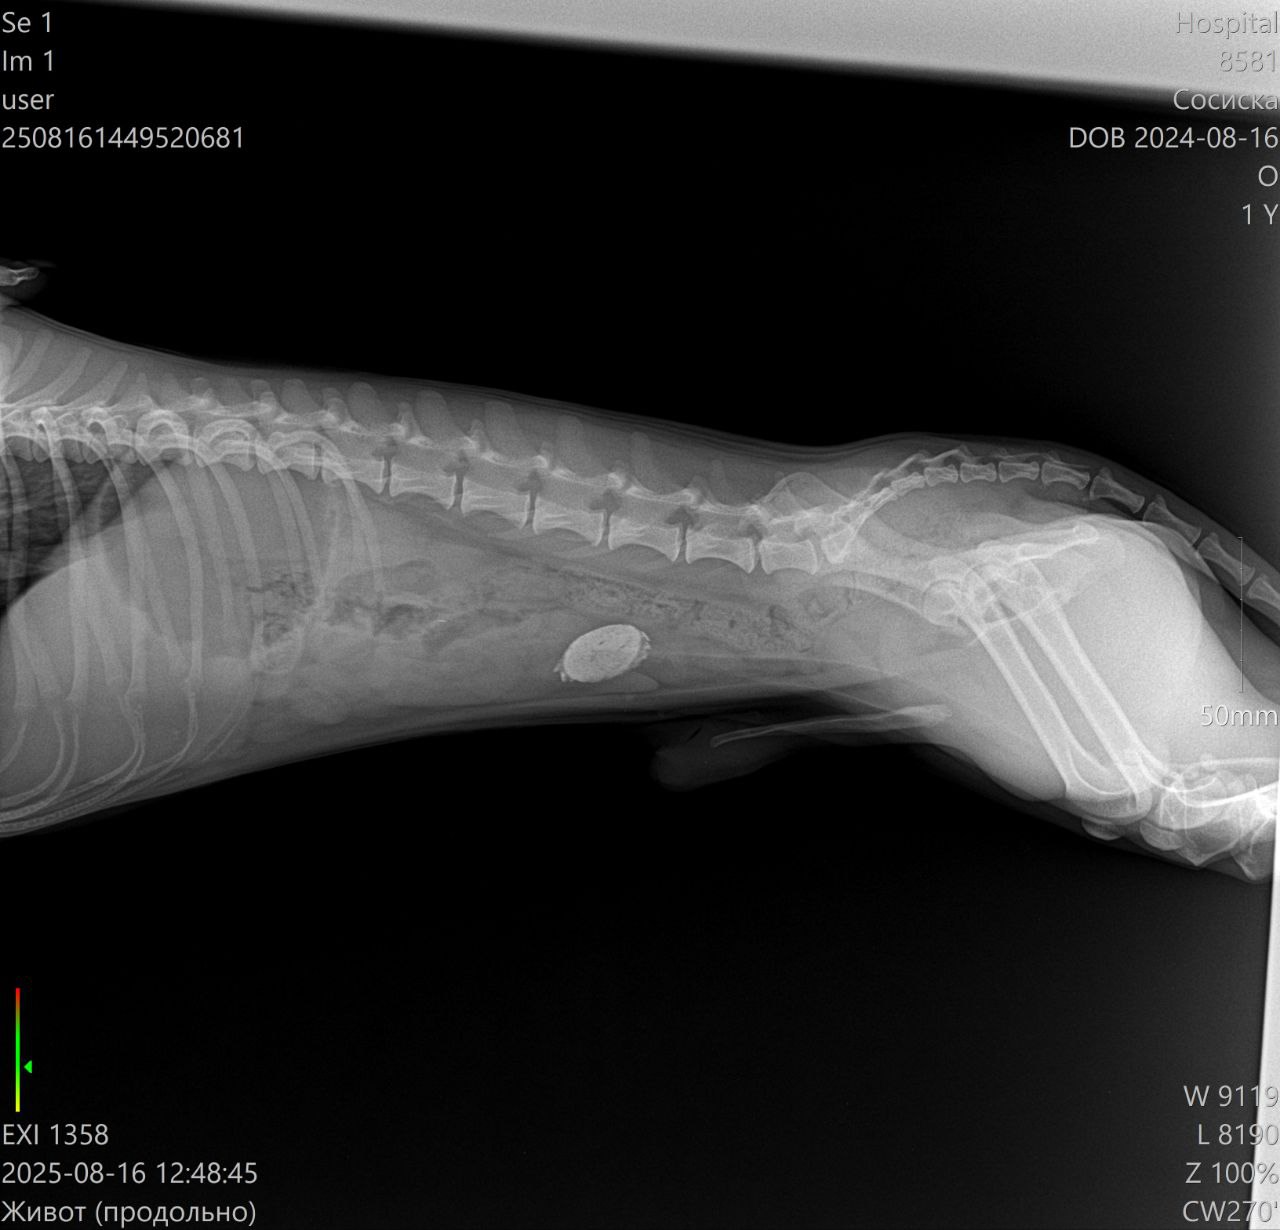

Ветеринарная клиника: измерение температуры, сделали УЗИ - в желудке обнаружена какая-то инородная штука, или показалось или... завтра на операцию

Клизмы и прочие смазки не уговорили отдать то ли крышку, то ли ещё что-то такое металлическое

Врачам пришлось резать сосиску и извлекать инородное тело